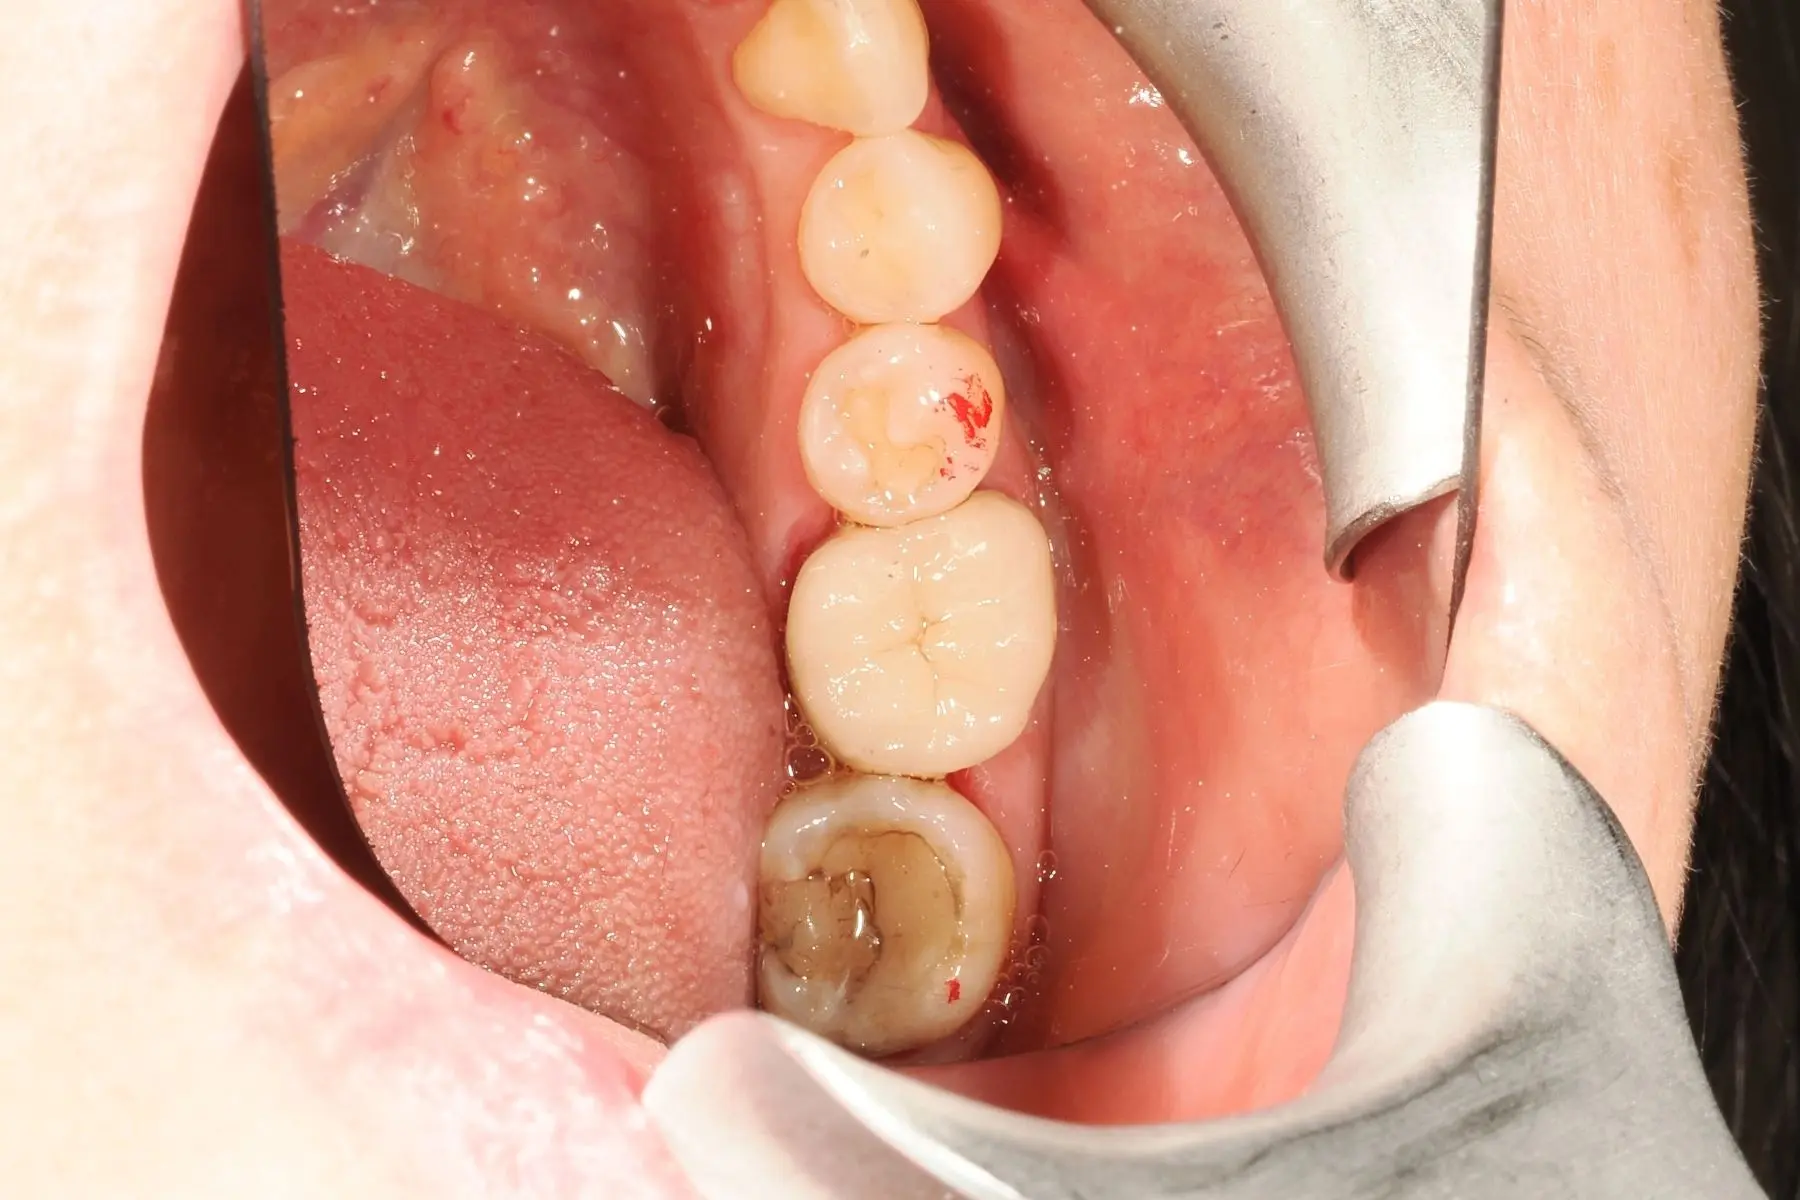

• 術前 30

術後 29

3D齒雕

主治醫師

• 余子豪

治療時間

約3個月

主訴

右上牙齒咬東西時不適,影響咬合功能